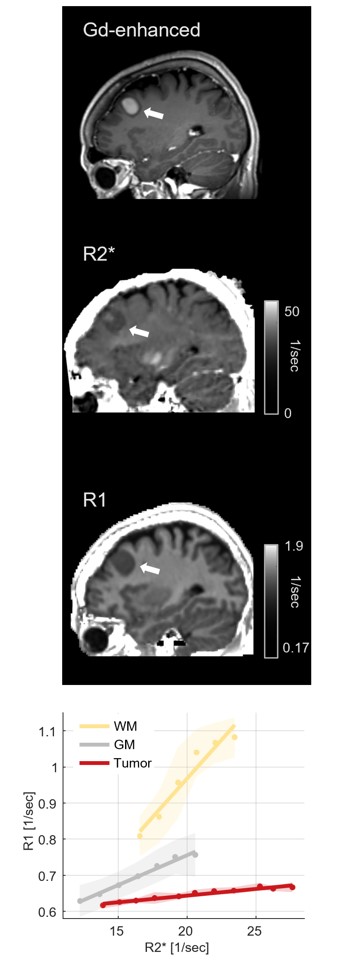

picture 3: : MRI image with contrast agent (Gd-enhanced), and quantitative MRI images (R1 and R2*) in a representative subject with a meningioma brain tumor (white arrow). Our new approach (in the bottom) separates between healthy tissue (WM and GM) and tumor tissue.